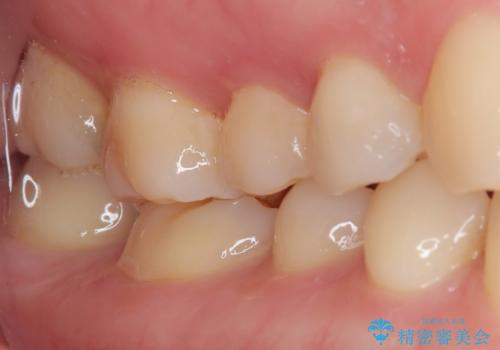

- 他院で虫歯を指摘され、精度の高い治療を希望されて来院された患者様です。

口腔内で直接処置を行う樹脂の材料(CR)で修復してありました。

フロスの引っ掛かりやレントゲン像から、CRを除去し、虫歯を徹底的に除去し、精度の高いセラミックインレーにて修復することとしました。